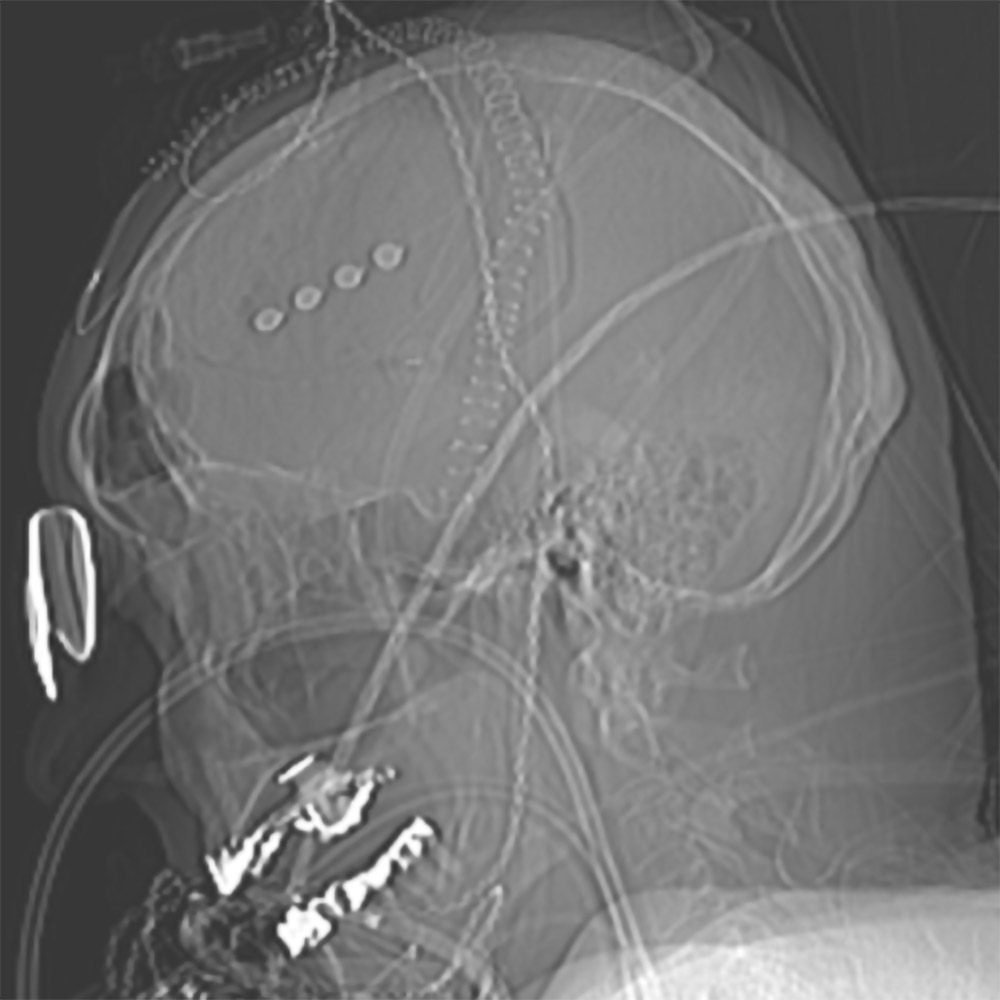

Auch PatientInnen mit akutem subduralem Hämatom (Blutung unter der Hirnhaut) erleiden häufig Krampfanfälle. Im Rahmen von Studien wird bei ihnen ein Dauer-EEG abgeleitet. Dafür erhalten sie EEG-Elektroden unter die Kopfhaut implantiert (siehe Bild). „Auch hier verfolgen wir die Fragestellung: Kann diese Datenanalyse mit künstlicher Intelligenz vorhersagen, ob und wann Anfälle auftreten? Falls ja, könnten wir rechtzeitig intervenieren und damit die Personen vor weiteren Verschlechterungen des Zustands schützen und präventiv behandeln?“, erklärt Professor Rosenow. Solche therapeutischen Ansätze basieren in der Regel auf Voruntersuchungen in Tiermodellen.